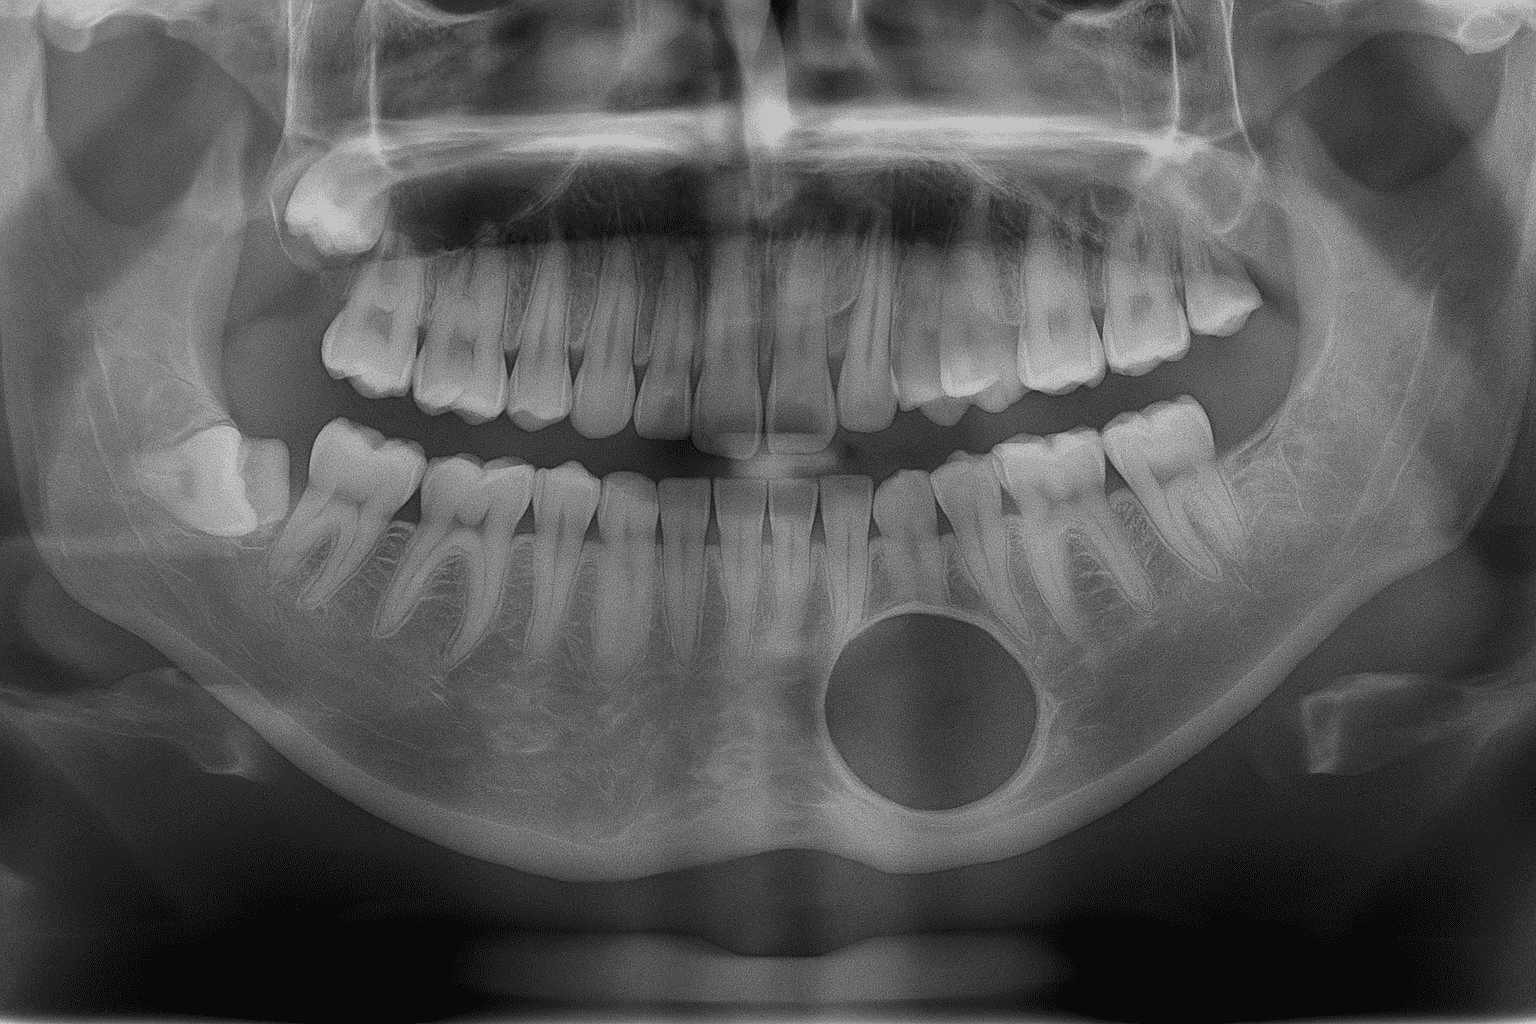

Impacted ToothImpacted teeth are teeth that remain in the jawbone and cannot come out into the mouth even though the time has come for them to erupt. The most common impacted teethare wisdom teeth, canines, and third molars.

Reasons:

jaw stenosis

Tooth development in the wrong direction

Gum or bone obstructions

Symptoms:

Swelling, pain, jaw locking

Pressure and crowding on neighboring teeth

Infection, cyst formation

Treatment: It is usually removed surgically. Early intervention reduces the risk of complications.

With regular dental checkups, impacted teeth can be detected and monitored in a timely manner.

Jaw Cysts: They are slowly growing pathological cavities filled with fluid or semi-fluid. They are most commonly seen in the jawbones. Because they are initially asymptomatic, they can be diagnosed late. Treatment is surgical; delays can lead to serious consequences such as facial deformity, inflammation, and tumor formation.

Jaw Tumors: It usually results from abnormalities in tooth development. It can be benign or malignant and requires surgical removal. The tumor's structure is determined by microscopic pathological examination, and treatment is planned based on these findings.